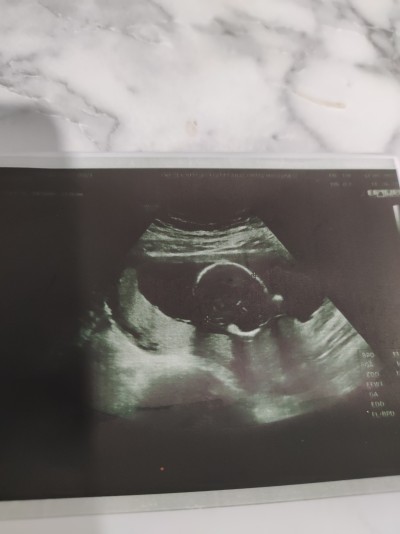

Merhaba arkadaşlar ultrason resminden anlayan varmı bunu verdiler ama anlayamadım sadece yuvarlak birşey var

Gebelik haftası 16+2

Kafa kısmı gibi duruyo üstten

Yok cnm cinsiyet değil 4 aylığa girdikten sonra böyle bi ulstrason verdiler normalde kafadan ayaklarına kadar veriyorlardı şimdi sadece bunu verdiler